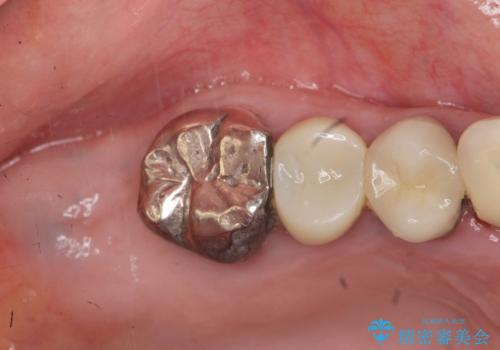

見た目の悪いクラウンをやりかえたい

- 色や形、適合の悪いクラウンの再治療を希望され来院されました。

装着されているクラウンを除去し、自然な色調のジルコニアクラウンによる審美生の改善、インプラントを用いた欠損部の機能回復を計画します。